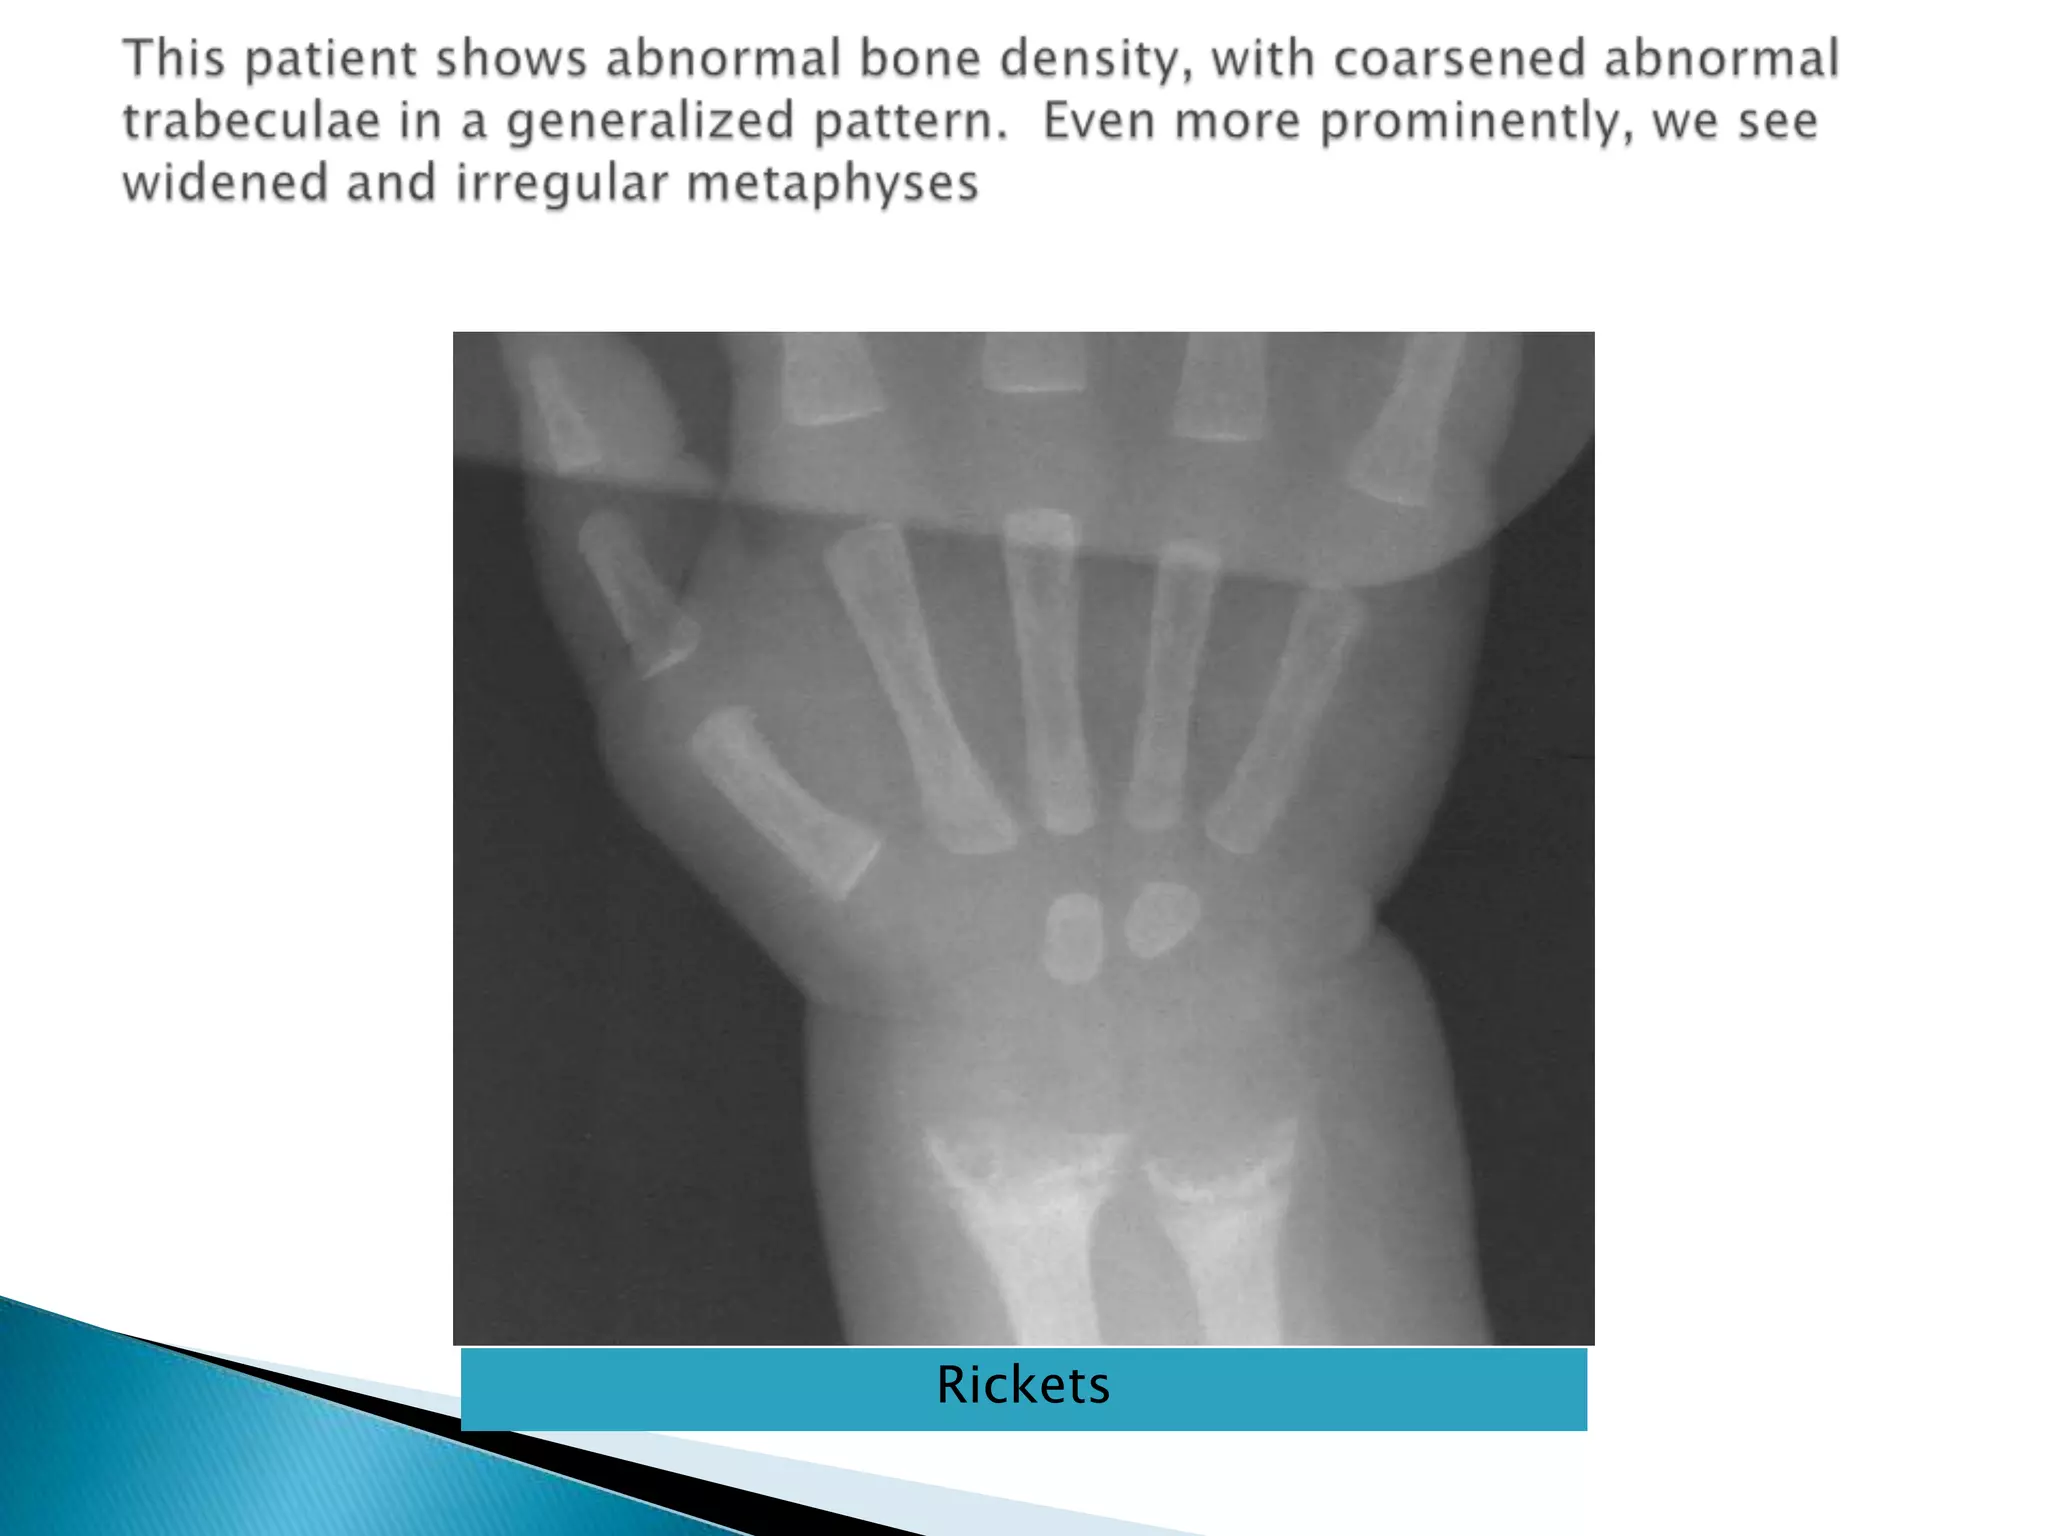

Radiological finding of ricketsThe changes are  maximal where bone growth is occur, so they best seen in the knees, wrists & anklesLoss of provisional zone of calcification.Indistinct metaphyses& metaphyses become irregular and cupped.Wide growth plate.decreased bone density.Deformities of the bones occur because of bone softening.Greenstick fractures are common

This patient shows abnormal bone density, with coarsened abnormal trabeculae in a generalized pattern.  Even more prominently, we see widened and irregular metaphysesRickets

Radiological finding ofricketsThe changes are maximal where bone growth is occur, so they best seen in the knees, wrists & anklesLoss of provisional zone of calcification.Indistinct metaphyses& metaphyses become irregular and cupped.Wide growth plate.decreased bone density.Deformities of the bones occur because of bone softening.Greenstick fractures are common

This patient showsabnormal bone density, with coarsened abnormal trabeculae in a generalized pattern. Even more prominently, we see widened and irregular metaphysesRickets